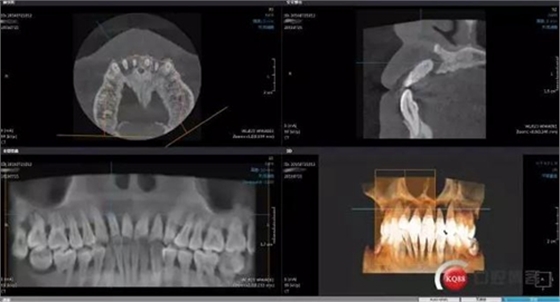

拔除上頜中切與側(cè)切牙同期GBR,手術(shù)中因?yàn)闆](méi)有拍照片僅拍術(shù)后CBCT有些小遺憾

GBR術(shù)后CBCT